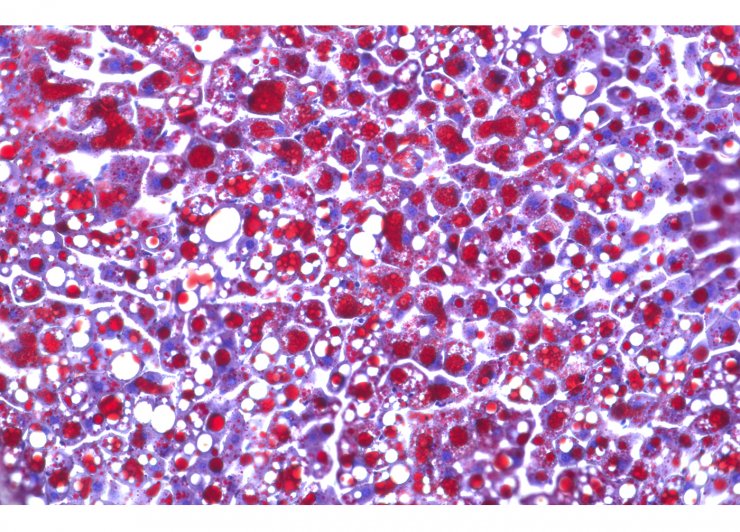

Bei Patienten, die langfristig mit entzündungshemmenden Steroiden behandelt werden, können sich Nebenwirkungen im Stoffwechsel bemerkbar machen. Forscherinnen und Forscher am Helmholtz Zentrum München und der Ludwig-Maximilians-Universität München (LMU), Mitglieder im Deutschen Zentrum für Diabetesforschung (DZD), konnten nun einen Mechanismus aufklären, der zu diesem sogenannten Steroid-Diabetes führt. Die Ergebnisse sind in ‚Nature Communications‘ nachzulesen.